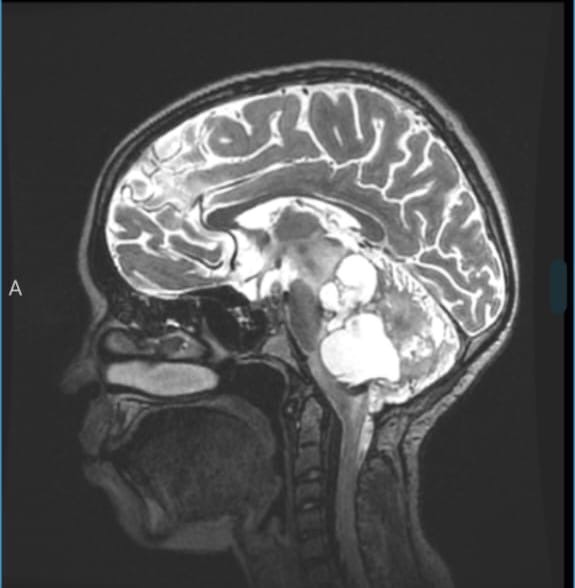

Luciana a los 11 años de edad fue diagnosticada con un tumor cerebral de gran tamaño llamado Astricitoma Pilocítico, posicionado en la base del tallo cerebral.

Fue intervenida quirúrgicamente por primera vez hace 3 años para colocar una válvula de derivación ventriculoperitoneal (VP), un mes después fue intervenida nuevamente para extirpar parte del tumor, y mediante un largo tratamiento de quimioterapia y radioterapia, se consiguió controlar el crecimiento de la masa ocupante.

Luciana was diagnosed at 11 years old with a large brain tumor called Pilocytic Astrocytoma, located at the base of the brain stem.

She underwent surgery for the first time then to place a ventriculoperitoneal shunt valve (VP). One month later, she was operated on again to remove part of the tumor, and through long treatment with chemotherapy and radiotherapy, they managed to control the growth of the occupying mass.